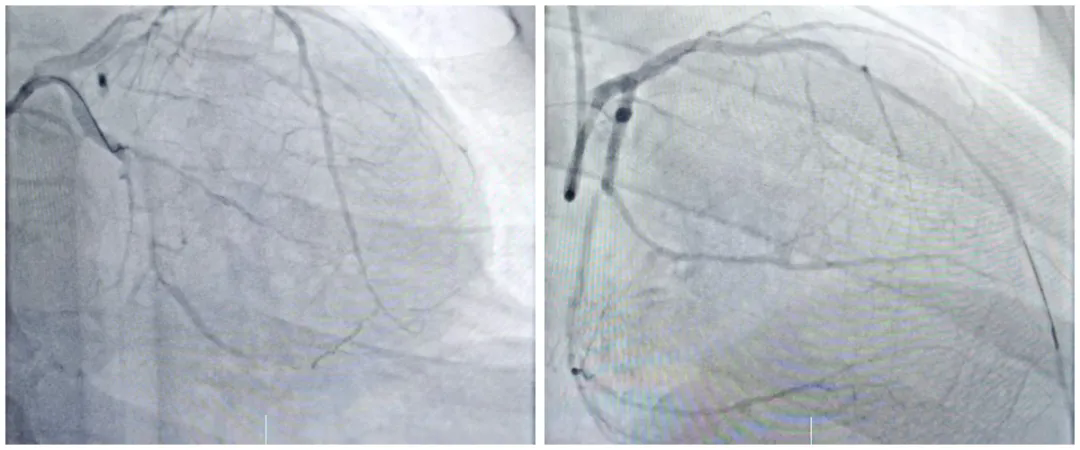

双支闭塞、多脏器受损,37岁重症冠心病患者重获“心”生

近日,我院心血管内一科团队成功为一名辗转多家三甲医院、濒临换心的37岁重症心脏病患者实施 IABP(主动脉内球囊反搏)支持下双支闭塞病变开通术,这场历时43分钟的精准手术,为患者重燃生命希望,展现了我院在重症心...